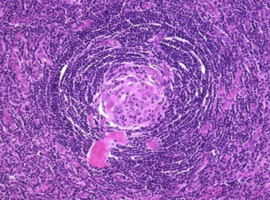

Unicentric Axillary Castleman Disease: A Case Report

Fischetti V*, Valerii C, Palamara F, et al. (Italy)